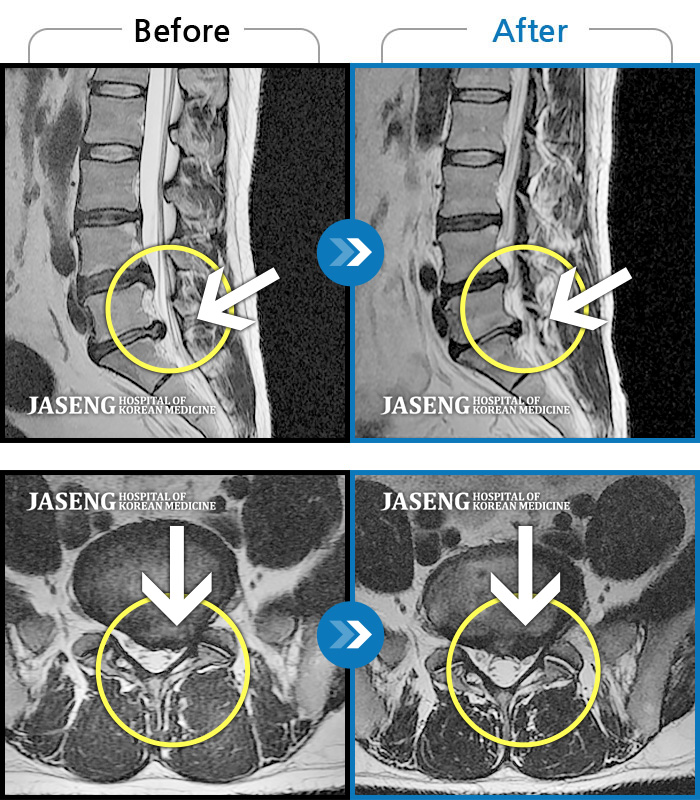

허리디스크

일산 · 김태용 원장

허리와 좌측 하지 방사통이 심하시어 보행이 거의 힘들었다.

촬영시기

2021.03.06 ~ 2021.07.15

2021.07.23